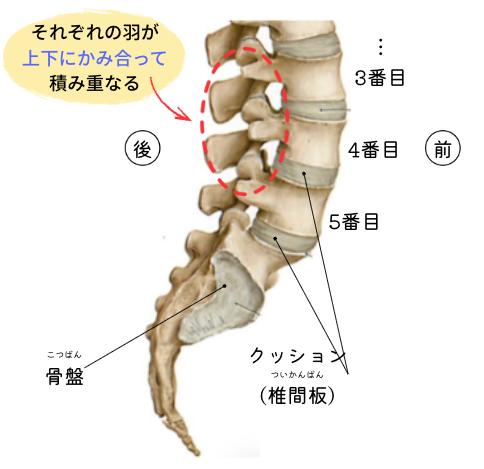

この腰のブロックは全部で5つあり、下から順番に5番目・4番目…と積み上げられ、間にはクッション(椎間板)が挟まっています。そして、それぞれがズレないように、羽が噛み合って固定されています。

この“噛み合っている”というのが今回のポイント。上の図の丸い点線で囲んだ部分がまさに噛み合っている部位なのですが、なんとなくこの羽の部分は腰が動いた際に上下でぶつかり合うような気がしませんか?腰椎分離症はこの羽同士がぶつかり合い、羽の根元が疲労骨折してしまった怪我になります。